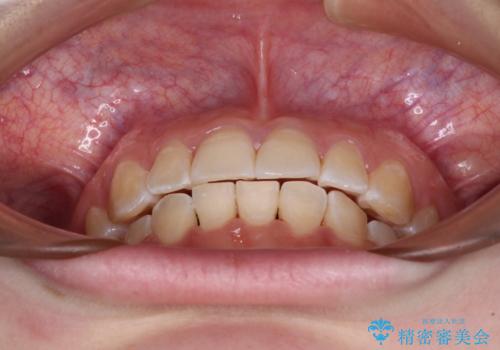

患者様も驚く、僅か10か月での治療終了となりました。

下顎前歯が1歯欠損しているため、上下正中は合わず、左右奥歯の咬み合わせは理想的とはならない仕上がりとなります。